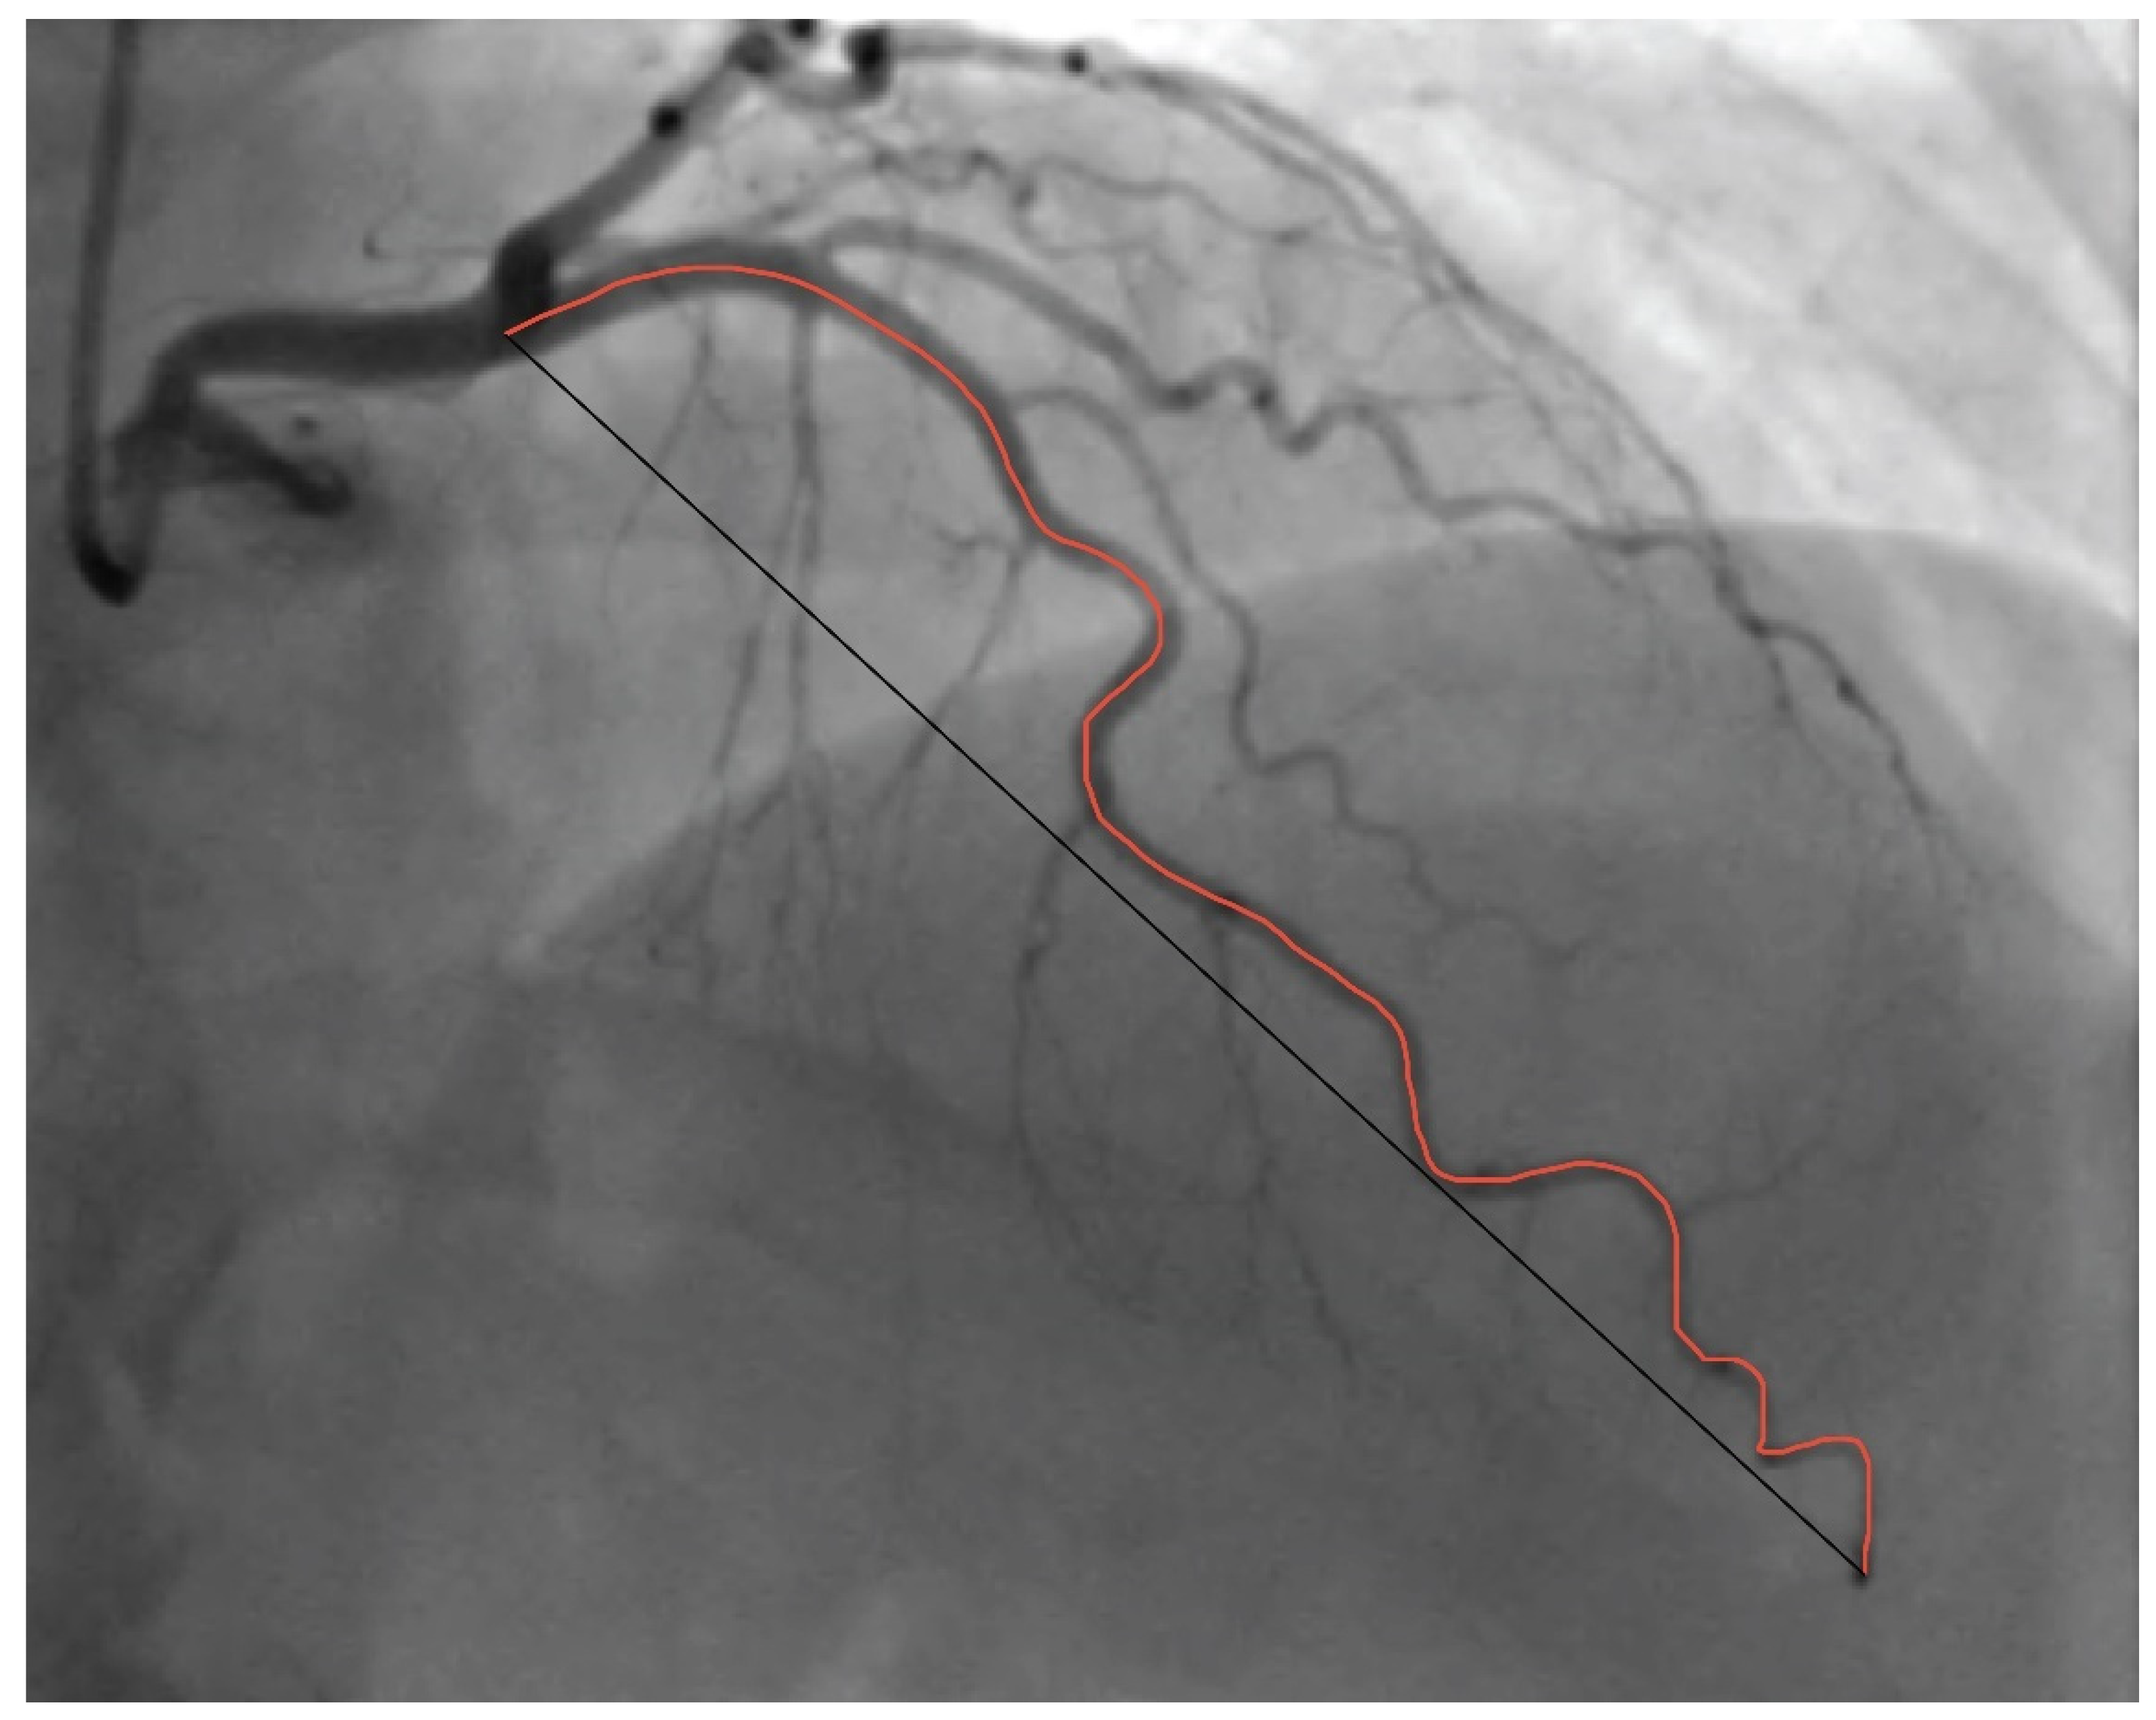

Coronary Tortuosity Index vs. Angle Measurement Method for the Quantification of the Tortuosity of Coronary Arteries in Non-Obstructive Coronary Disease

2. Materials and Methods